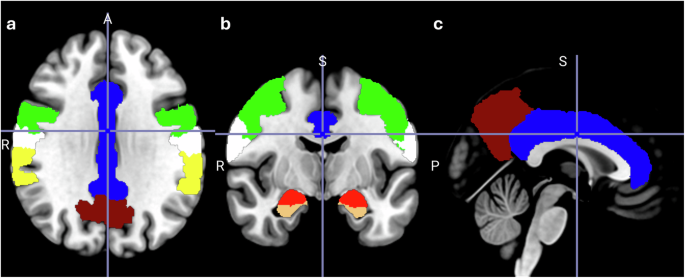

Across all studies, no matter the paradigm or analyses performed, probiotics seem to affect most often cingulate regions, hippocampal regions and supramarginal gyrus, with involvement in at least six comparisons (probiotic vs placebo). Additionally, exclusively in the fMRI analyses, precuneus, pre- and postcentral gyrus and amygdala were involved in four comparisons (probiotic vs placebo). Generally, frontal regions seem to be affected quite often in the studies included in this review. The regions that are most commonly affected by probiotic interventions are visualised in Fig. 1. Of note, since the majority of studies applied whole-brain analyses approaches (Supplementary Table 9), it can be assumed that probiotic interventions generally evoked stronger signal changes in those reported brain regions. Probiotic-induced changes in the included EEG and MEG studies, independent of whether they were conducted during rest, sleep or during task performance, most often showed an impact on theta brain waves, which are indicative of early stages of sleep or drowsiness. Interestingly, the combined findings of this review are consistent with the results of studies that correlate brain connectivity and gut microbiota composition63,64. In a systematic review of 16 such studies, the authors found associations between brain connectivity in the salience (most prominently the insula and cingulate cortex), default mode, and frontoparietal networks and gut microbiota composition and diversity, with low specificity likely due to the heterogeneity of the included studies65. Our systematic review on probiotics’ effects as a potential gut microbiome modulating intervention now adds towards the understanding of directionality and causality.

Brain regions most commonly affected by probiotic interventions. Regions are presented on a standard brain in a axial, b coronal, c sagittal view. Probiotics most often affected the highlighted brain regions: hippocampus (orange), cingulate gyrus (blue), supramarginal gyrus (yellow), precentral gyrus (green), postcentral gyrus (white), amygdala (red), precuneus (brown) - across all studies, independent of paradigm applied, technology used or analyses performed.